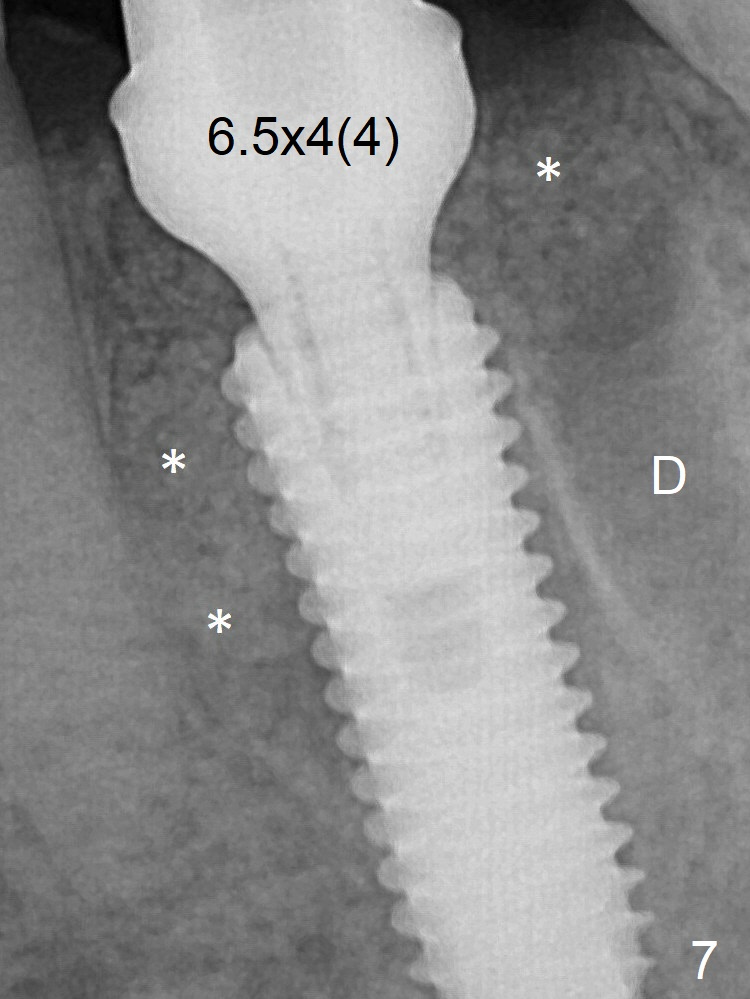

Due to severe buccal plate resorption, a shorter implant is placed (Fig.6; 5x15 mm in stead of 18 mm).  There is at least 2 mm gap buccally for Vanilla Graft, which is also placed next to the implant and the neighboring root (Fig.7 double * ).  Abutment: 6.5x4(4) mm.  The distal (D) socket is packed with Collagen Plug before bone graft coronally (single *).  Both the mesial and distal sockets heal 5.5 months postop (Fig.9), although the apical portion of the distal socket was not filled with allograft (Fig.7 D).  The implant was placed mesial.  The abutment may be changed to 5.5x5(3) mm or 4.5x15 degrees 3 mm cuff before impression.  Next case, osteotomy should be established in the middle of the socket by using Lindamann bur amply.